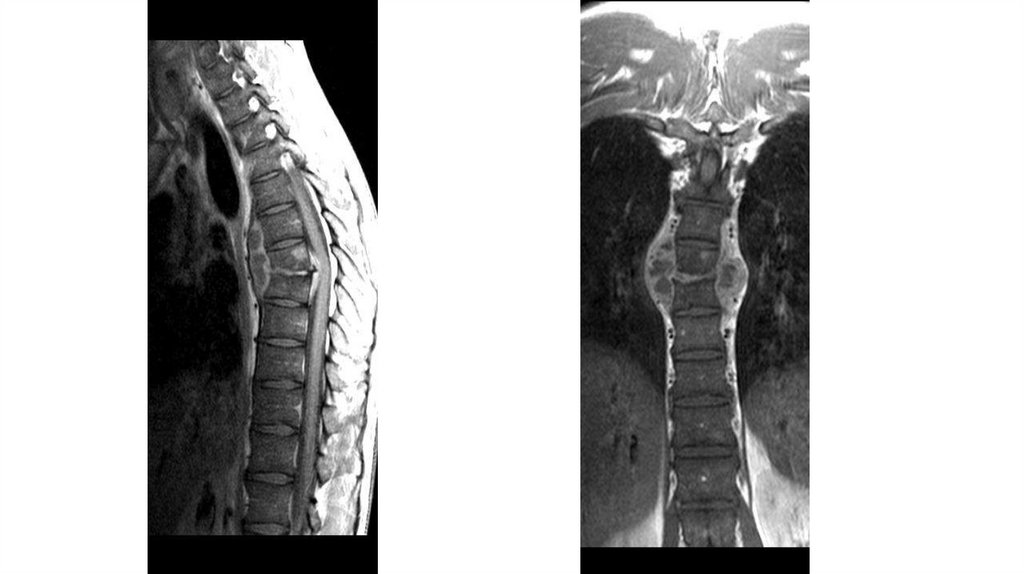

Воспалительные заболевания опорнодвигательного аппарата

«Воспалительные

заболевания опорнодвигательного аппарата»